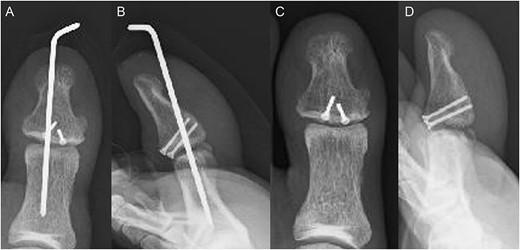

A 54-year-old man injured his right great toe while walking and wearing sandals. He complained of tenderness, swelling, and pain during motion. He could bear weight but could not actively extend the interphalangeal (IP) joint of the hallux. He was referred to our outpatient clinic 3 days after the injury. Physical examination revealed swelling, tenderness, and motion pain, and the patient could not extend the IP joint of the hallux. Plain lateral radiography and computed tomography revealed a displaced avulsion fracture of the dorsal base of the distal phalanx (Fig. 1). Surgery was performed under general anesthesia after informed consent was obtained on posttraumatic day 11. A Y-shaped incision was made at the center of the dorsal IP joint, and the displaced bony fragment was attached to the extensor hallucis longus (EHL). The IP joint was temporarily fixed with a 1.6 mm Kirschner wire, and the fragment was repositioned and fixed with two 1.5 mm cortical screws (APTUS® Hand, Medartis, Basel, Switzerland). A 4-0 FiberWire® (Arthrex, Naples, FL, USA) was fastened as an augmentation proximally to the EHL tendon and distally to the periosteum of the distal phalanx in a figure eight (Fig. 2). Postoperatively, the ankle was externally fixed in dorsiflexion from the leg to the toe, and heel loading was permitted. A total of 4 weeks after surgery, the Kirschner wire was removed to allow active motion of the IP joint of the hallux, and weight bearing was allowed on the hallux 5 weeks postoperatively. Plain radiographs taken 3 months after surgery confirmed bone healing (Fig. 3). A total of 20 months postoperatively, the patient acquired normal function, and the range of motion of the affected IP joint ranged from −3° to 30°, with no difference from the unaffected side (Fig. 4). Skin necrosis or nail deformities were not observed.

Plain radiographs (A) anterior–posterior view and (B) lateral view show an avulsion fracture of the dorsal base of the distal phalanx. Plain computed tomography (C) sagittal slice and (D) axial slice reveals an avulsion fracture of the dorsal base of the distal phalanx similar to the plain radiograph. Additionally, the fracture length line of the fragment was 5 mm.